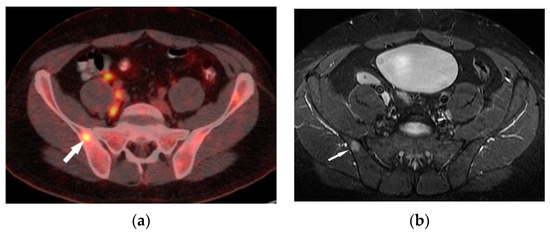

MR is a highly sensitive imaging modality that can detect bone marrow involvement in sarcoidosis. It also provides the detailed information on soft tissue involvement, synovitis and joint inflammation. Occasionally, MR images detect clinically and radiologically silent lesions (Figure 3a,b).

A decrease in the FDG uptake in the follow-up PET/CT study is indicative of a metabolic response associated with regression of the sarcoid foci. A promising diagnostic tool for musculoskeletal sarcoidosis appears to be a hybrid of PET and MRI [16] (Figure 4a,b).

Figure 4. FDG-PET/CT (a) and T1–weighted MRI image with contrast enhancement (b) presents an enhanced lesion with increased FDG uptake (white arrows) in the right iliac bone.